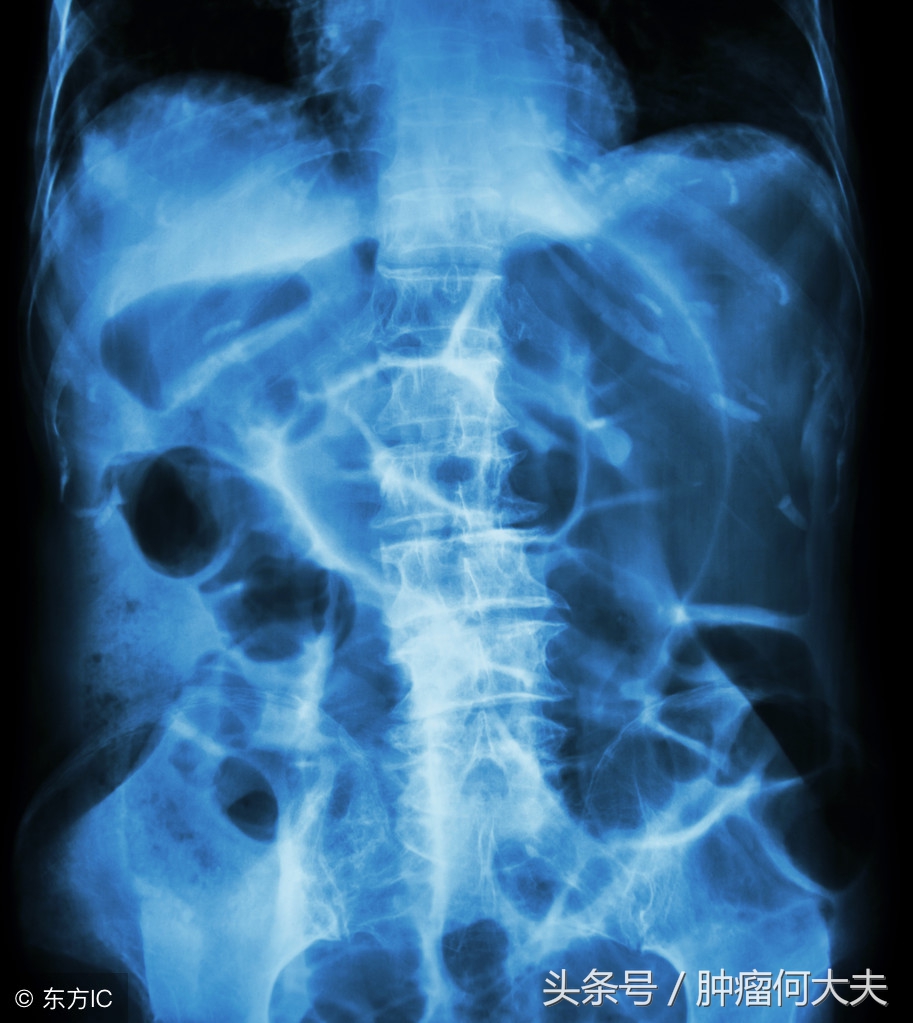

术后王先生恢复期一直很长,食欲不振,伴乏力,腹胀,曾一度出现小肠梗阻,第一次梗阻是中午吃了还没有泡透发开的木耳,饭后约1个多小时就出现了轻度腹痛,未重视晚上还吃了一些面条,半夜腹部疼痛加剧并呕吐,于手术医院就医时被诊断为肠梗阻。医生下胃管,禁食,禁水,静脉补液以维持营养,口服石蜡油不长就排出一堆像煤渣一样的排泄物,肠子终于通了。

一周前王先生再次因腹胀伴发热,收住院,入院后化验检查提示①有感染,白血球偏高;②小肠梗阻,。造瘘袋每天有稀水样粪便排出,但量不多。在禁食,禁水,下胃管,负压引流同时,口服石蜡油,给予全肠外静脉营养支持,2天后患者腹胀未见明显缓解。后决定通过造瘘口处理,当时找了一根长约30厘米的尿管,后将尿管沿造瘘口插入,后用50ml注射器回抽,先抽出两管稀水样粪便,无明显臭味,抽第三管时候有阻力,后抽出小拇指大小的蔬菜叶团块(已经压缩在一起,但周围有菜叶样子,依然能看出它的原型),这个小蔬菜疙瘩被抽出后,哗哗的流出约有800ml稀便,而且粪水奇臭无比,此后患者腹胀明显好转,发热也逐渐好转。王先生回忆自己吃过炒空心菜。

肠梗阻

肠癌病人,其中有不少都被迫造瘘,造瘘术后,大便改道不仅给患者带来生活上的麻烦,需要定期进行造瘘口袋清洁置换,而且有的患者由于造瘘口位置高,尤其是回肠造瘘,饮食不关注就会出现肠梗阻,弄不好也可能会致命。回肠造口是回肠末端在腹壁的开口。人体消化道的每一部分都发挥着重要的作用。食物在人的胃内形成食糜,在小肠内通过进一步消化,小肠能够吸收食物中绝大部分的营养,而结肠负责吸收水分,使便成形。回肠造口术后,消化的食物不再经过大肠,容易再经过腹壁的肠道时被截留,一旦发生这种情况,大概率就会阻塞。食物阻塞的结果就是,可能引起腹部痉挛,腹痛,腹泻等,饮食需要关注的是避免难以消化的食物,包括干果,椰子,红肉,菌类,空心菜,芹菜,豆角等食物。除饮食因素外,肠造口病人也要关注情绪因素,临床发现不少造口病人伴有抑郁症,抑郁态势会下调人体免疫力,导致病情复发。而开朗外向积极向上的精神态势有助于病情康复。